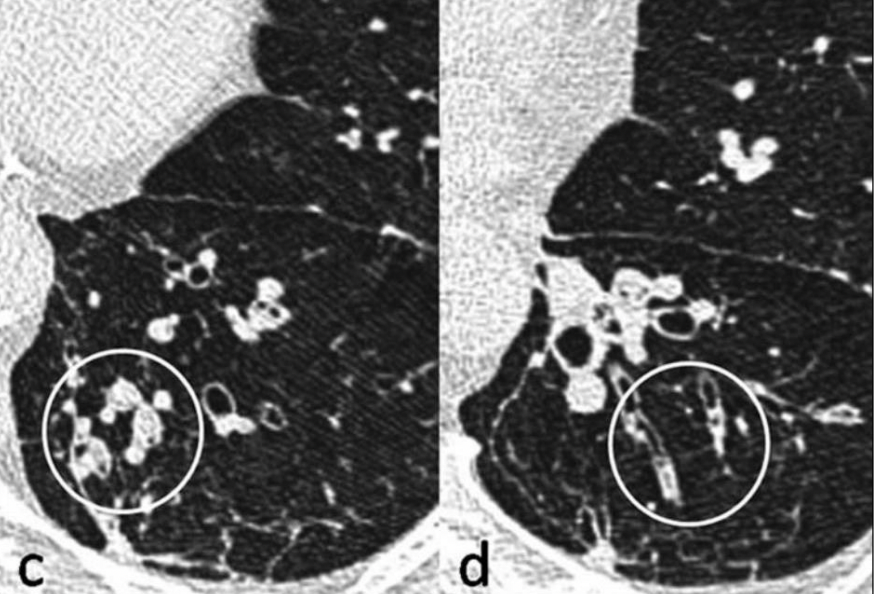

Centrolobulillar

Panlobulillar

Paraseptal